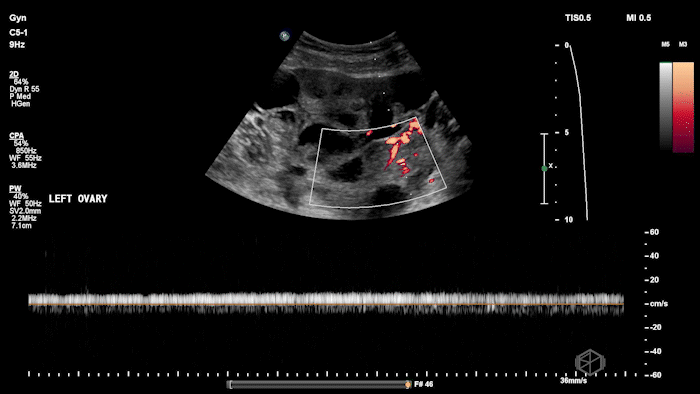

She grabbed the probe, and working with Dr. Zimmerman, saw the following:

There is moderate free fluid, no obvious pleural effusions. The bilateral ovaries are enlarged with multiple cystic structures. There are normal arterial and venous waveforms for both ovaries.

• Typical ultrasound findings: enlarged ovaries with multiple cysts/follicles; free fluid (ascites) and in more severe cases pleural or pericardial effusions. (📚 PMID: 27998636)

• Preserved ovarian arterial and venous flow helps distinguish OHSS from acute ovarian torsion, where flow may be compromised.